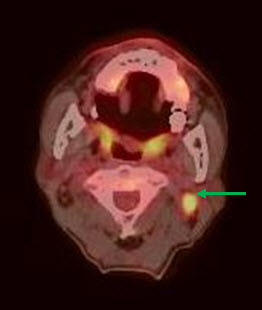

Trước điều trị: hình PET/CT thấy khối u thanh quản (mũi tên vàng) và hạch cổ trái (mũi tên xanh) tăng hấp thu FDG mạnh. SUV u thanh quản = 5,31; SUV hạch cổ = 4,87

Sau hóa xạ trị: u và hạch biến mất, trên hình PET/CT không thấy các tổn thương này nữa.

Hình 1. Bệnh nhân Lê B. L., nam, 66 tuổi. Chẩn đoán: Ung thư thanh quản (ung thư biểu mô tế bào vảy) di căn hạch cổ. Bệnh nhân được chụp PET/CT để đánh giá giai đoạn trước điều trị và mô phỏng lập kế hoạch xạ trị; sau khi được điều trị hóa chất và xạ trị (IMRT) bệnh nhân được chụp lại PET/CT để đánh giá kết quả điều trị. Kết quả cho thấy bệnh đáp ứng hoàn toàn.